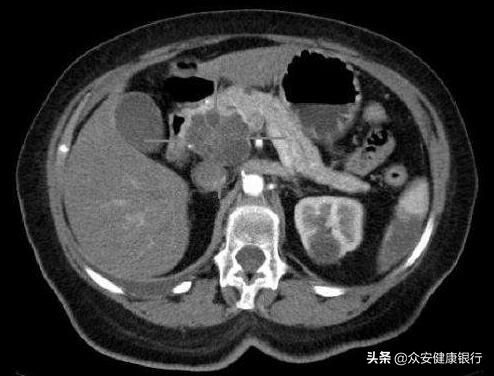

图片来源:public domain